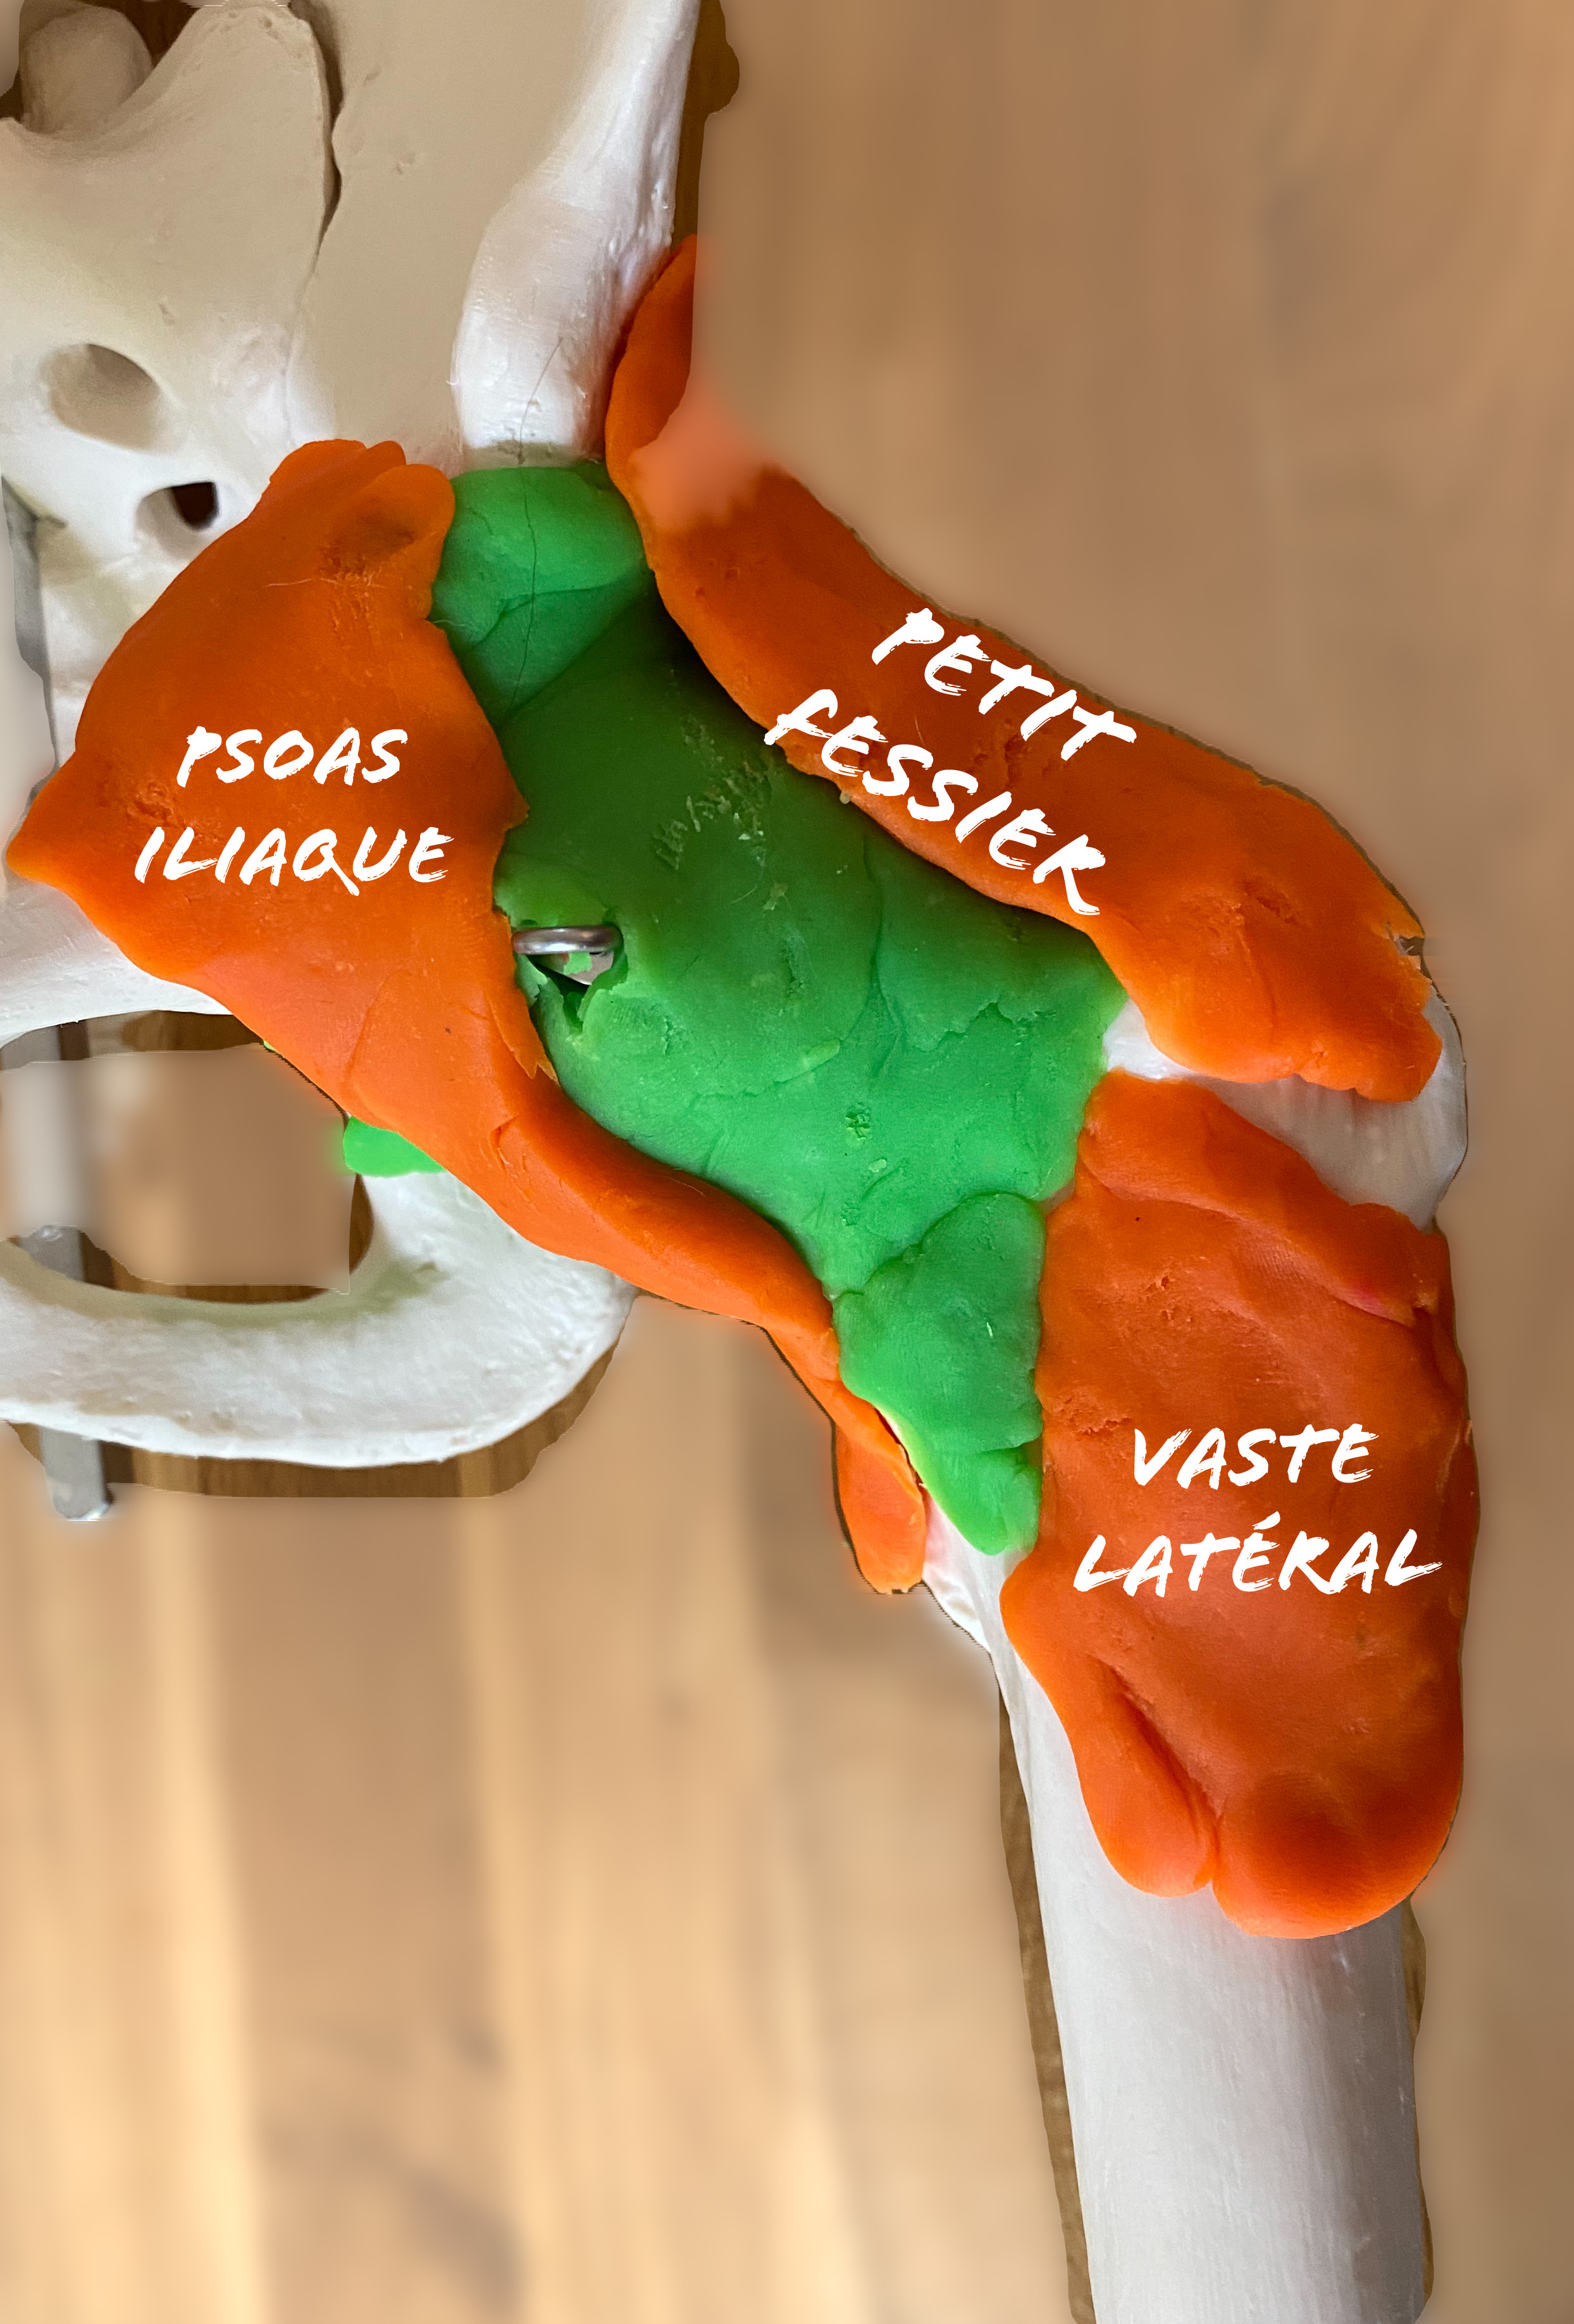

Il existe plusieurs manières de mettre en place cette prothèse selon la localisation de l’incision, et les structures traversées et/ou « ouvertes ».

L’avantage de cette voie sont le respect des structures musculaire (passage entre les muscles), la diminution du taux de luxations, et une récupération réputée plus rapide .